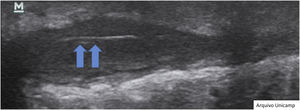

During the examination, the probe should be gently positioned perpendicular to the lesion, as shown in Fig. 1.27 It is important to apply little pressure and stabilize the hand with the help of the fifth finger. Image capture must be done in two perpendicular axes, covering both the lesional and perilesional areas.8,10,14,17,22 If necessary, one can compare the images with others obtained from the contralateral area.